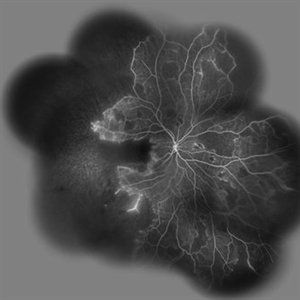

Behcet's Disease Behcet's DiseaseMar 13 2013 by Hamid Ahmadieh, MD Wide field FA of the right eye of a 23-year-old man with retinal vasculitis and branch retinal vein occlusion (BRVO) due to Behcet's disease . Photographer: Solmaz Shahmohammad, Negah Eye Center, Tehran Imaging device: Heidelberg Spectralis Condition/keywords: branch retinal vein occlusion (BRVO), retinal vasculitis